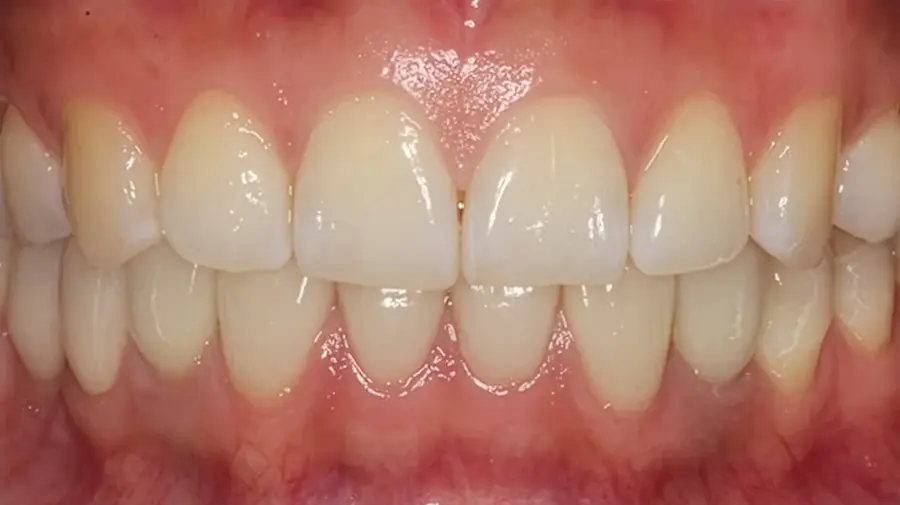

Una vez integrado, se coloca la pieza dental definitiva, diseñada para reproducir forma, color y función de los dientes naturales.

La diferencia de recuperar tu sonrisa

«No estamos sustituyendo dientes, estamos devolviendo la capacidad de disfrutar de un buen momento alrededor de una mesa sin preocupaciones.» — Dr. Esteban Balabanian